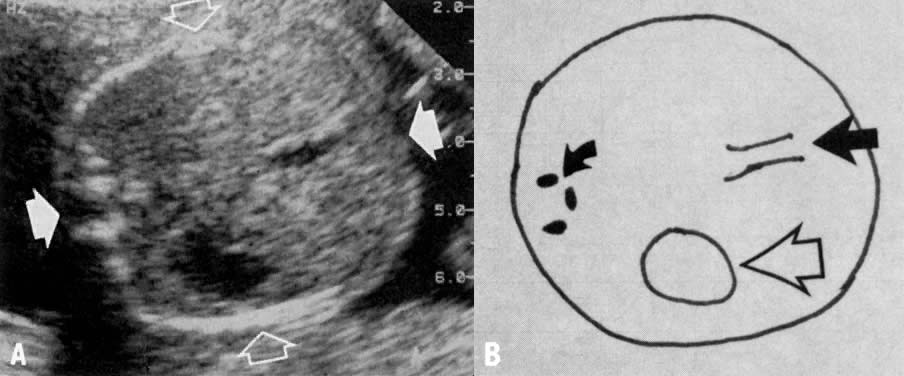

Other limitations in evaluating growth by BPD include: imprecision in the estimation of birth weight; poor detection rate of asymmetrically undergrown babies, with normal or near normal cephalic size; and changes in head shape such as side-to-side flattening or dolichocephaly. This condition may occur in some pregnancies during the third trimester, rendering the BPD artificially small (Fig. 3). In such situations, unless HC is substituted for BPD, false abnormal diagnoses of IUGR can be made.

Fig. 3. Some side-to-side flattening of the fetal head or dolichocephaly is noted. However, the cephalic index is only slightly below 1 SD from the mean. In the presence of severe dolichocephaly the head circumference should be substituted for the BPD.(Sabbagha RE: Intrauterine growth retardation. In Sabbagha RE [ed]: Diagnostic Ultrasound Applied to Obstetrics and Gynecology, 2nd ed, p 118. Philadelphia, JB Lippincott, 1987)